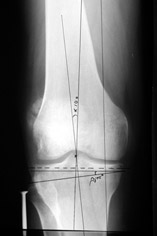

AC> Вот, с учетом и без учета, и на разных уровнях...

AC> Саша Артемьев, может, для данного случая свой вариант нарисуешь?

Из приведнной схемы не совсеим понял что означают разноцветные линии.

И зачем латерализация периферического фрагмента. Я всегда делаю медиализацию. См схему. И для данного случая медиализация подходит как нельзя лучше.

a> Из приведнной схемы не совсеим понял что означают разноцветные линии.

Черные - это нынешняя механическая ось. Красные - это планируемая правильная ось.

a> И зачем латерализация периферического фрагмента.

;-) Читайте Палея. Стр. 114-115.

a> Я всегда делаю медиализацию. См схему. И для данного случая

Медиализация - это чисто эстетический прием, как я понимаю. Поскольку если делать остеотомию ниже вершины деформации, для восстановления оси надо делать смещение по ширине, в данном случае как раз латерализацию.

А вот на схемке без осей - там на разных уровнях (который правильнее?) устранение варуса чисто открытым клином без медиализации-латерализации. Если как-то так сделать - этого недостаточно будет?